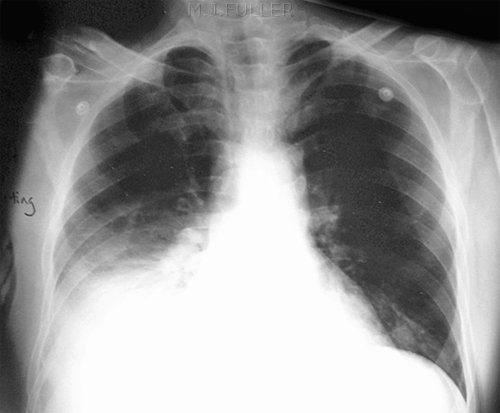

Example 2

Take a look at the following example showing consolidation. Click on the box to reveal the diagnosis.

Diagnosis

Right Upper Lobe Pneumonia